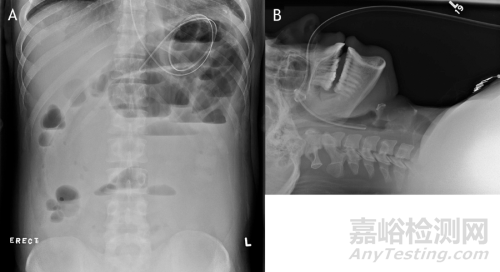

通過(guò)國(guó)家藥品不良反應(yīng)監(jiān)測(cè)中心及FDA-MAUDE、Pubmed數(shù)據(jù)庫(kù)查詢到該產(chǎn)品有多起疑似不良事件。經(jīng)鼻腸營(yíng)養(yǎng)導(dǎo)管產(chǎn)品在臨床中出現(xiàn)的問(wèn)題主要有:堵管、不通暢;連接處脫落;刻度標(biāo)記不清、錯(cuò)誤;打折、末端開裂;接頭斷裂/脫落/不匹配;石蠟油潤(rùn)滑管體后刻度標(biāo)記消失;消化道黏膜損傷;導(dǎo)管拔出困難、拔出過(guò)程在患者鼻咽部發(fā)生打結(jié)等(如圖6所示)。

圖6 導(dǎo)管打結(jié)的X光照片

A.導(dǎo)管在患者體內(nèi)發(fā)生卷曲;B.導(dǎo)管拔出時(shí)在鼻咽部打結(jié)